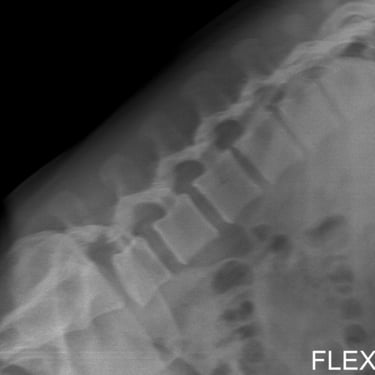

Listesis Lumbar L5–S1 por Fractura Ístmica: Estabilización con FTP y TLIF

La listesis lumbar L5–S1 por fractura ístmica se produce por un defecto en la pars interarticularis que genera inestabilidad vertebral, dolor lumbar crónico y compromiso radicular. Cuando el tratamiento conservador no es efectivo, la artrodesis lumbar con fijación transpedicular (FTP) asociada a la fusión intersomática transforaminal (TLIF) es una alternativa quirúrgica eficaz. Este procedimiento permite descomprimir las raíces nerviosas, restaurar la alineación vertebral y lograr una fijación sólida del segmento afectado. La combinación de estabilización y fusión reduce el dolor, mejora la función y favorece una recuperación segura y progresiva.